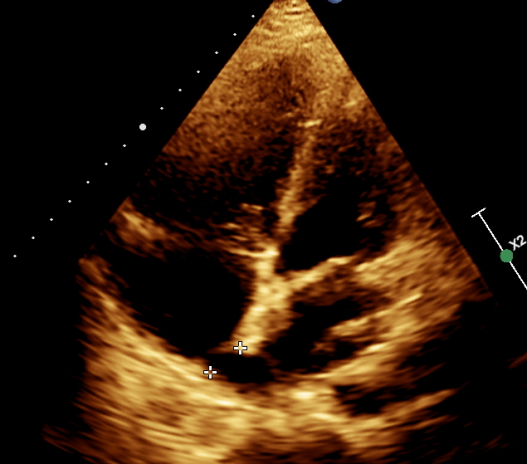

图 1 四腔心切面显示房间隔上可探及宽约 13mm 回声失落,房顶部未见明显

图 2 四腔心切面显示至少两支肺静脉引流入左房